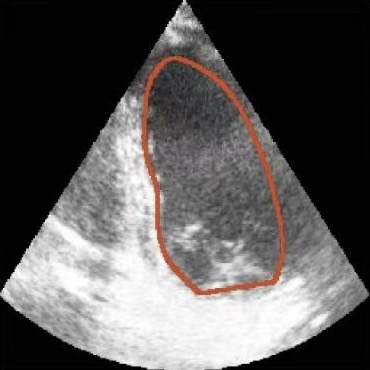

Figure 1: Illustrative challenges for echocardiography video segmentation: (a) speckle noise, (b) indistinct or blurred contours, and (c-f) the substantial changes in the target’s shape and scale throughout the cardiac cycle.

However, achieving precise segmentation in echocardiography faces severe challenges stemming from poor image quality and complex cardiac dynamics. Figures 1(a) and 1(b) show that ultrasound images are characterized by high speckle noise and low contrast, which obscure tissue structures and lead to weak or incomplete anatomical boundaries. These artifacts hinder the model’s ability to learn robust features and can result in the inaccurate segmentation. In the temporal dimension, the heart undergoes significant non-rigid deformation throughout the cardiac cycle. Figures 1(c), 1(d), 1(e) and 1(f) show that, the shape and scale of the LV change dramatically between systole and diastole. This substantial dynamic variation demands that segmentation models possess strong temporal modeling capabilities to accurately track the changing appearance of the target across the video sequence [20].